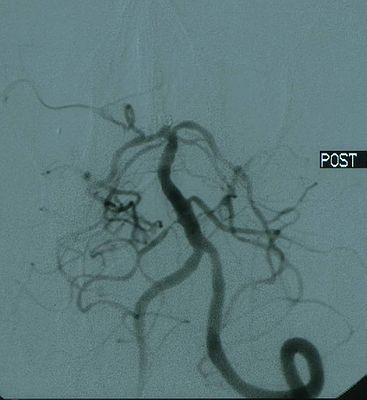

② 微创血管内介入栓塞动脉瘤。七十年代中期有人发明了用介入方法治疗颅内动脉瘤,当时使用的材料 主要为球囊,但临床效果不佳;八十年代开展了用游离弹簧圈栓塞治疗颅内动脉瘤,通过导管将弹簧圈放入动脉瘤囊内,使其闭塞,但游离弹簧圈可操作性和安全性较差,经常有弹簧圈脱出等问题;到了九十年代,新的电解可脱式弹簧圈(GDC)问世,使动脉瘤的栓塞治疗安全而可靠,治愈率达95%以上。21世纪初,又有人将血管内支架结合GDC来治疗那些宽颈的或梭形的颅内动脉瘤,以往单纯GDC难以治愈的动脉瘤,取得了明显的成功。因此,几乎可以说任何部位、任何形状的动脉瘤都可以通过介入栓塞的方法来治疗。

血管内介入栓塞治疗动脉瘤,以其创伤小、痛苦少、恢复快、疗效稳定、急诊出血期也能进行、年老体弱者也能承受告等优点,广受动脉瘤患者的喜欢。

动脉瘤栓塞后